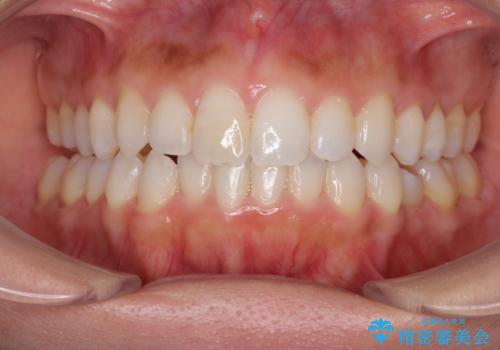

- 上下の前歯のデコボコと奥歯の反対咬合を気にして来院された患者様です。

インビザラインを用い、上下顎ともにIPR(歯と歯の間を削る)により叢生を改善することとしました。

治療を長期化させたくないとのご要望があったので、左下の90度捻転した歯は、捻転した状態のゴールとしました。

反対咬合を改善したことで、歯ぎしりしたときの引っかかる感じがなくなり、奥歯への負担を大きく軽減することができました。